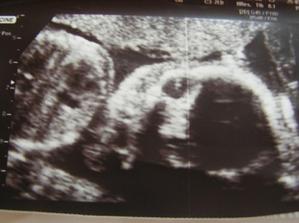

27.5.2009 (30.týden, 60kg) - druhý velký ultrazvuk: potvrdili nám holčičku. Tentokrát více spolupracovala, šlo to krásně vidět. Pěkně roste. Vše je v pořádku, maličká se už otočila hlavičkou dolů.